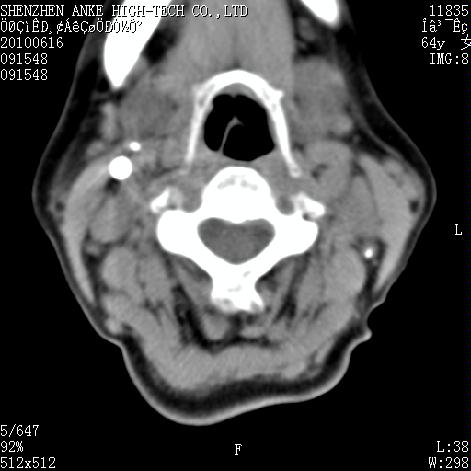

标题: CT27132:患者女,64岁,颈部及全身多处包块,现觉吞咽困难4 [打印本页]

标题: CT27132:患者女,64岁,颈部及全身多处包块,现觉吞咽困难4

右侧甲状腺占位,肿瘤可能性大,癌

右侧甲状腺癌伴右颌下腺淋巴结转移

右侧甲状腺癌伴淋巴结转移

右侧甲状腺癌伴淋巴结转移可能性大

右侧甲状腺癌伴淋巴结转移可能性大。

右侧甲状腺癌伴右颌下腺淋巴结转移!建议增强!